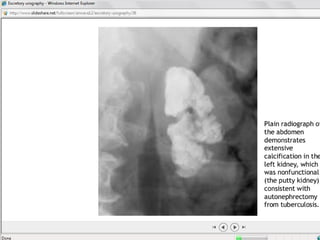

GU Tb-plain KUB

Disparity in renal size on plain films may indicate

early increase in size of the affected kidney due to

caseous lesions or a shrunken fibrotic kidney of

autonephrectomy.

Calcifications are seen in 30% to 50%

A characteristic diffuse, uniform,extensive

parenchymal, putty-like calcification, forming a lobar

cast of the kidney is seen with autonephrectomy

Calculi may also be seen in the collecting system or

ureter secondary to stricture formation.

 Ureteral calcifications are rare and are

characteristically intraluminal as opposed to the mural

. Bladder wall calcifications seen in late cases of

bladder contraction.

 Calcifications of the prostate and seminal vesicles are

seen in 10% of cases .

Plain film findings suggestive of tuberculosis may be

seen in surrounding tissues such as erosions of the

vertebral bodies or calcifications in a cold abscess of

the psoas muscle.